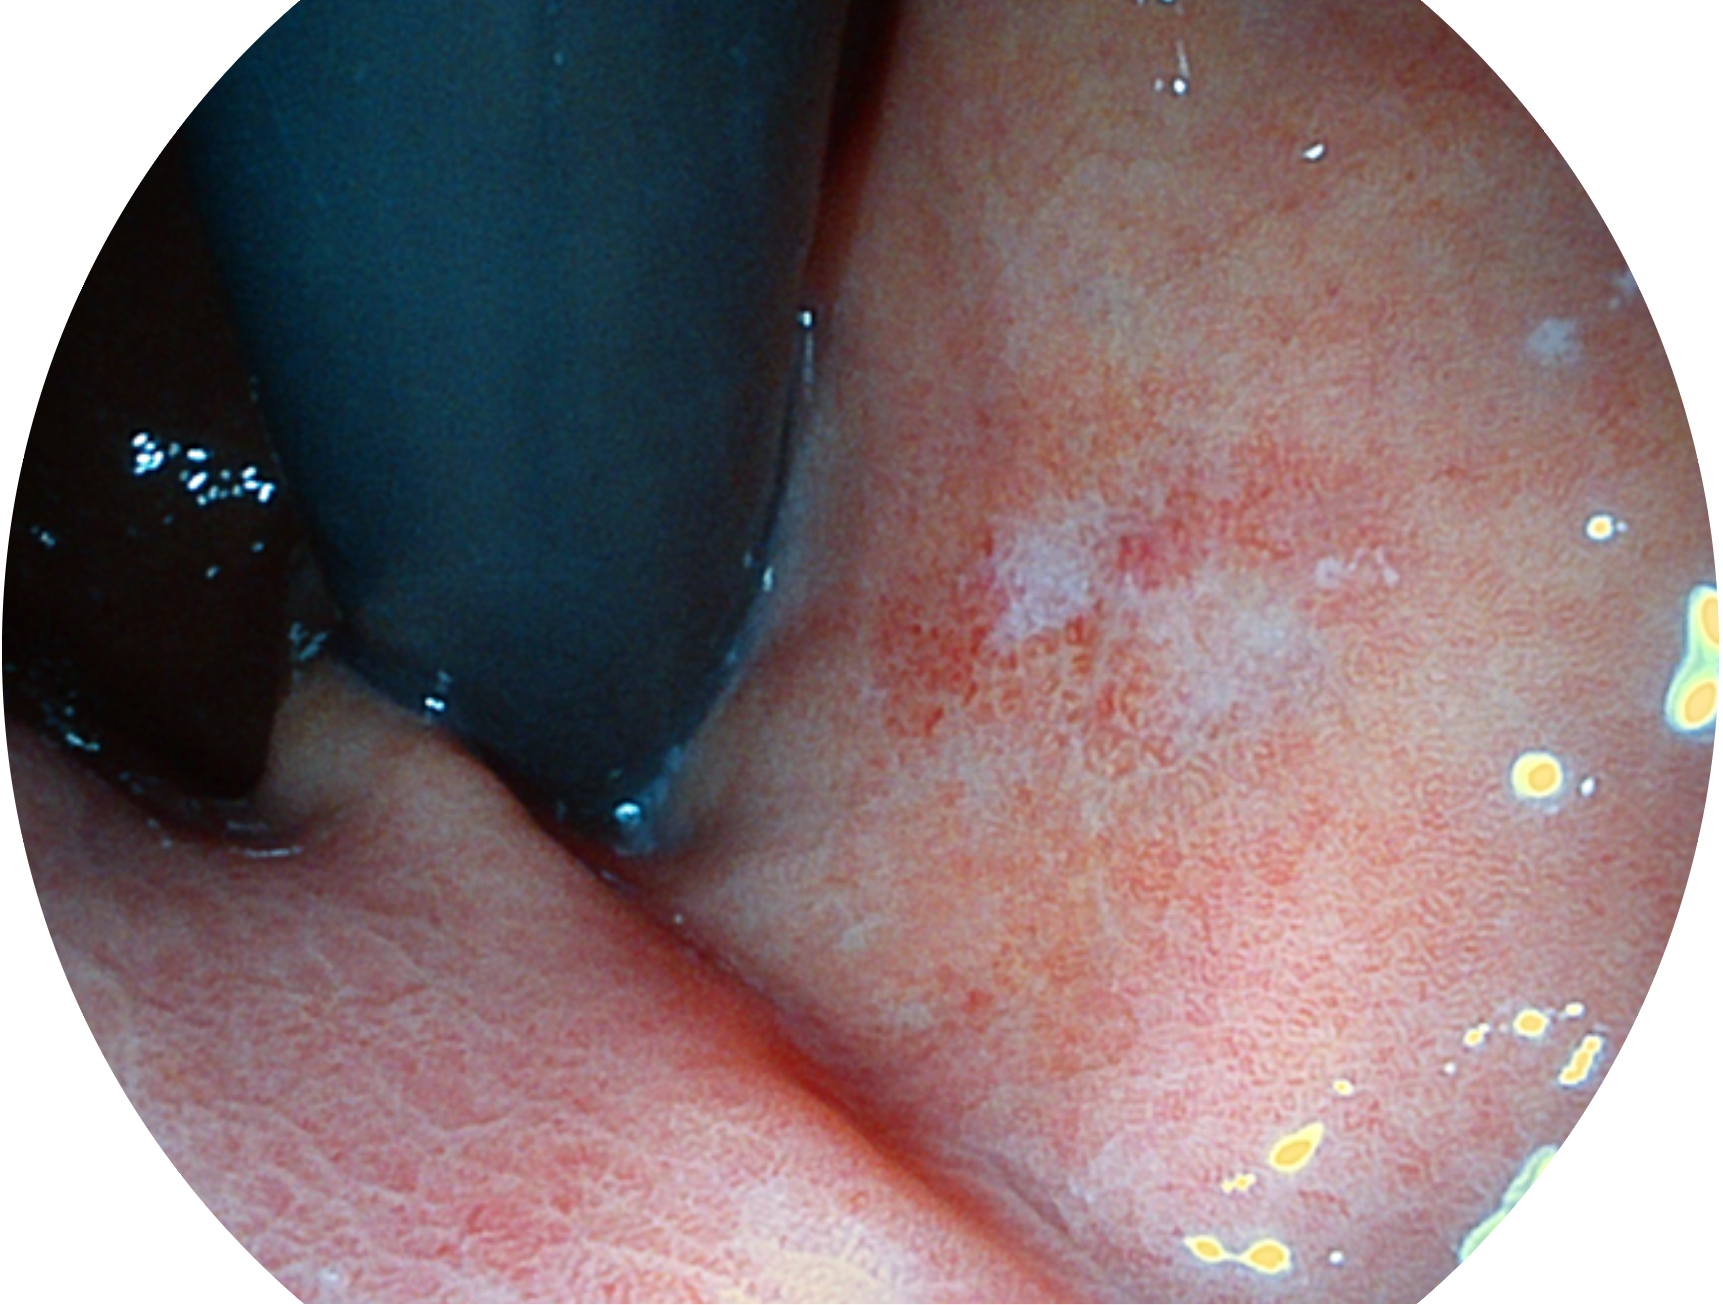

玖鼎集团新开发的内镜染色技术,主要是基于多波长LED 光源的开发,VLS-55Q 四波长LED 光源是由四个不同颜色的LED光按照相应照明模式所规定的特定发光比例进行合束后形成,合束后形成的照明光的光谱由红光、绿光、蓝光及蓝紫光这四个不同的波段范围构成。具有更高光谱自由度,通过光谱比例的控制,实现了聚谱成像技术,英文全称为“Spectral Focused Imaging, SFI”,缩写为“SFI”和光电复合染色成像技术,英文全称为“Versatile Intelligent Staining Technology, VIST”,缩写为“VIST”。